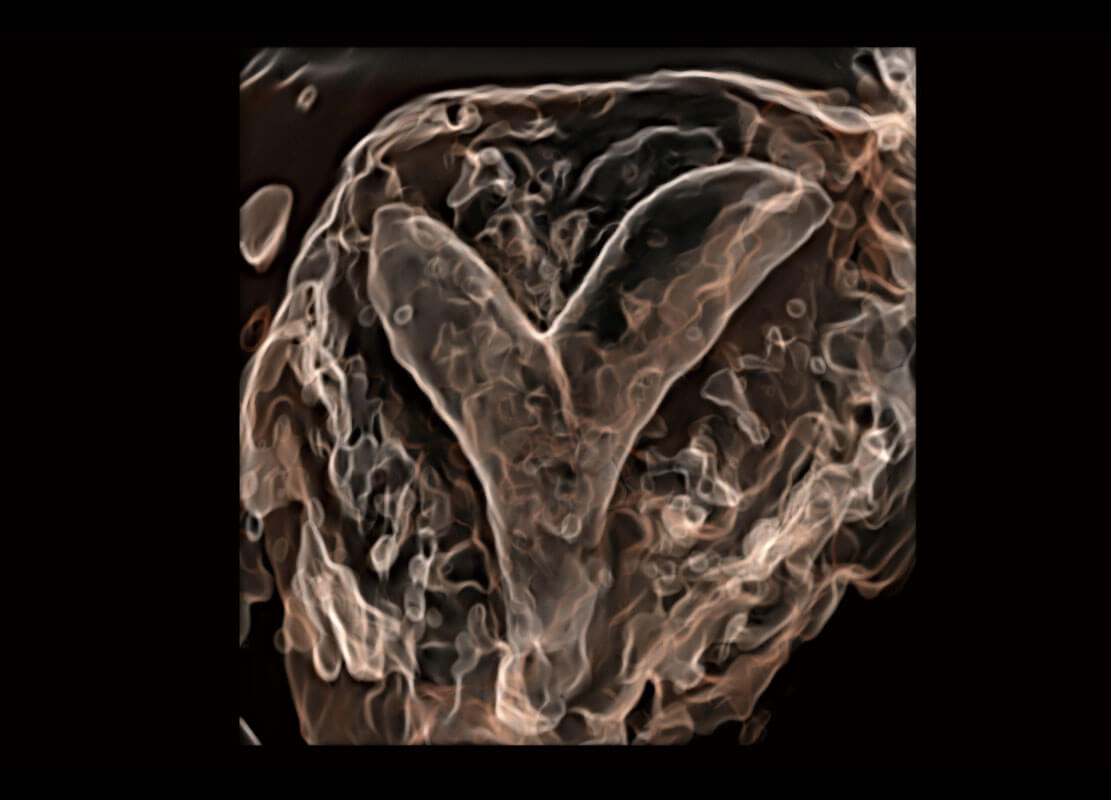

生殖健康

P60优异的图像质量搭载专科探头,在妇科基础疾病的诊断、卵泡生长的监测、输卵管通畅情况的判别等方面为您提供生殖应用方案。

• 腔内妇科-宫腔分离

• 腔内妇科-卵巢

• 腔内三维-宫内节育器

• 腔内三维-光影成像